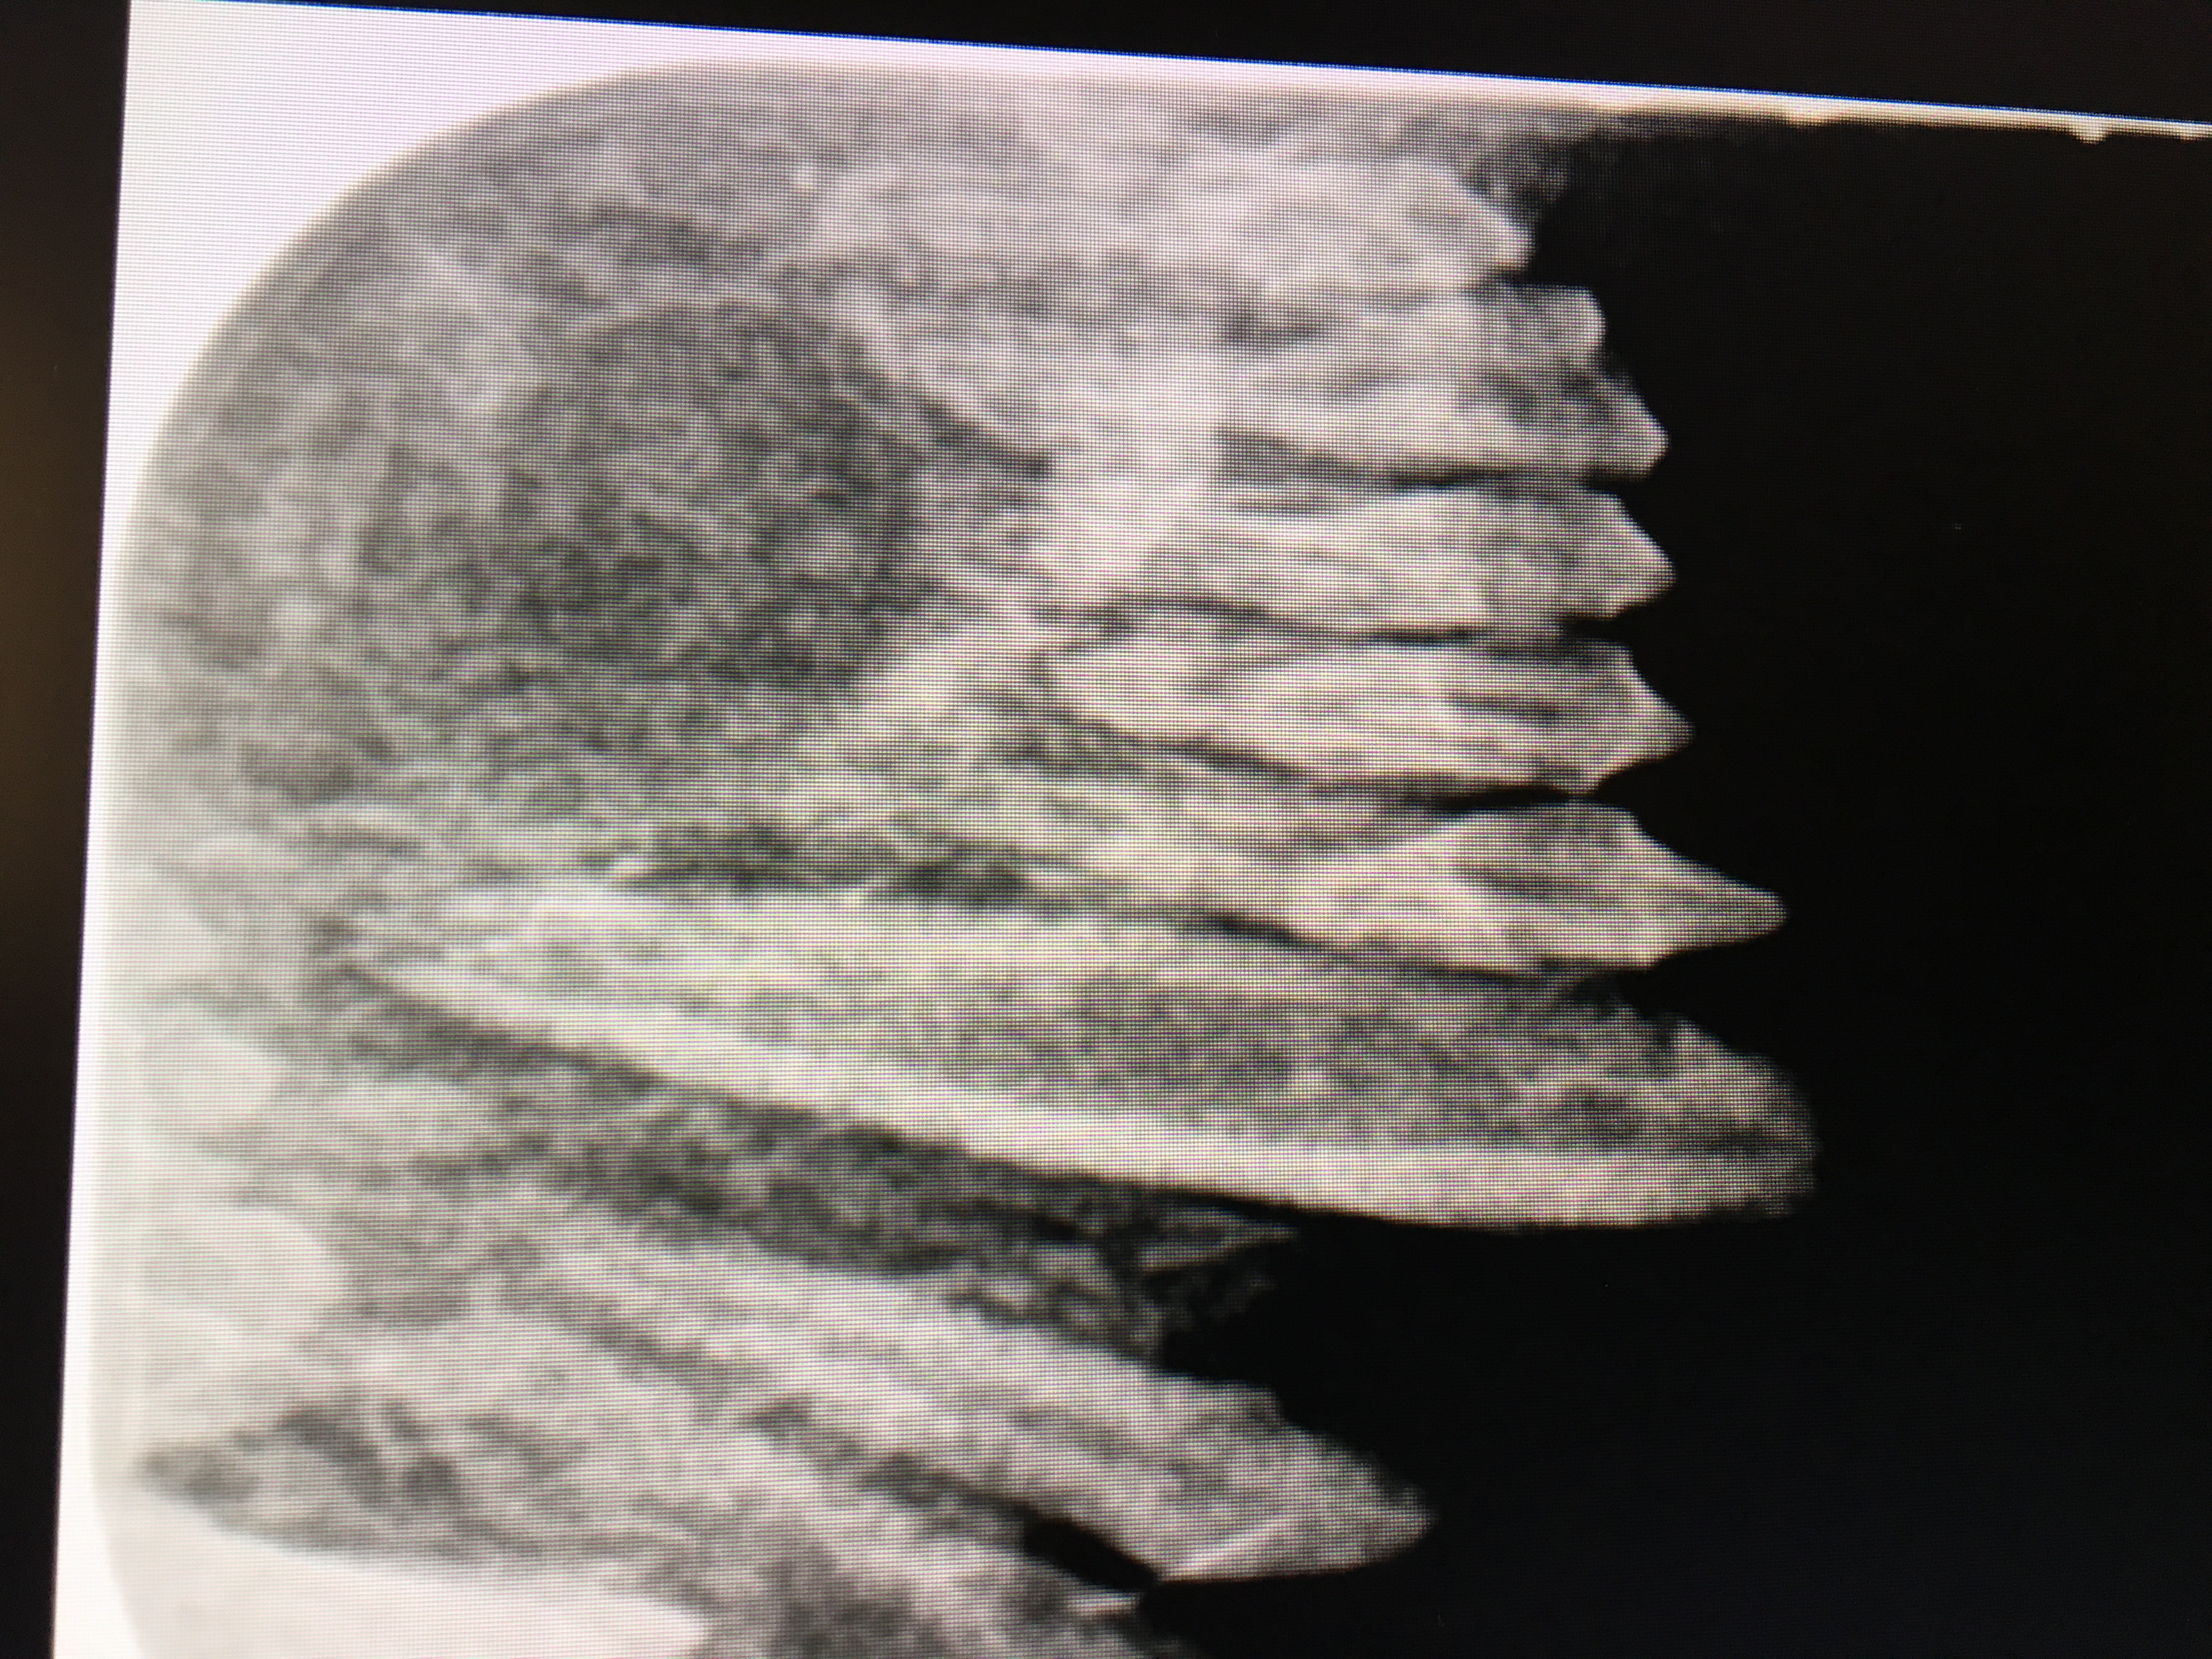

A 2022 Cotton Top Tamarin maxillary canine endodontic procedure is an example of successful endo case that avoided a surgical extraction for this very small patient. A working length radiograph revealed with file in place at 11 mm. showed that the file had gone beyond the apex. 8mm. was chosen as the proper working length and the endo procedure was completed. See fill radiograph.